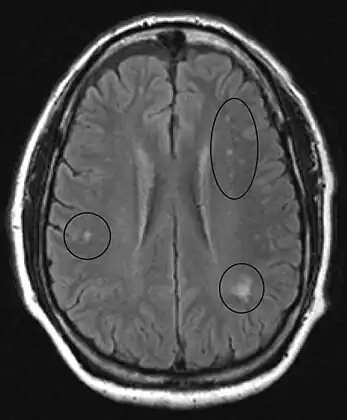

MRI of the brain may show periventricular white matter abnormalities. MRI of the spinal cord may show linear hyperintensity in the posterior portion of the cervical tract of the spinal cord, with selective involvement of the posterior columns.

MRI image of the brain in vitamin B12 deficiency, axial view showing the "precontrast FLAIR image": note the abnormal lesions (circled) in the periventricular area suggesting white matter pathology. -